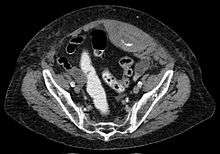

Rectus sheath hematoma seen on axial CT - with active bleeding under Marcoumar

A rectus sheath hematoma is an accumulation of blood in the sheath of the rectus abdominis muscle. It causes abdominal pain with or without a mass.

The hematoma may be caused by either rupture of the inferior epigastric vein and in rare case epigastric artery or by a muscular tear. Causes of this include anticoagulation, coughing, pregnancy, abdominal surgery and trauma. With an ageing population and the widespread use of anticoagulant medications, there is evidence that this historically benign condition is becoming more common and more serious.[1]